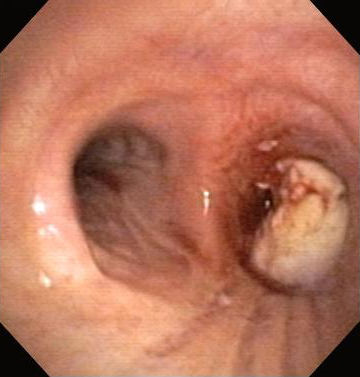

Обструкция нижних дыхательных путей: злокачественная обструкция правого бронха

Из коллекций Хосе Фернандо Сантакруза, дипломированного врача, члена Американской коллегии специалистов в области торакальной медицины, DAABIP, и Эрика Фолка, дипломированного врача, магистра наук; используется с разрешения